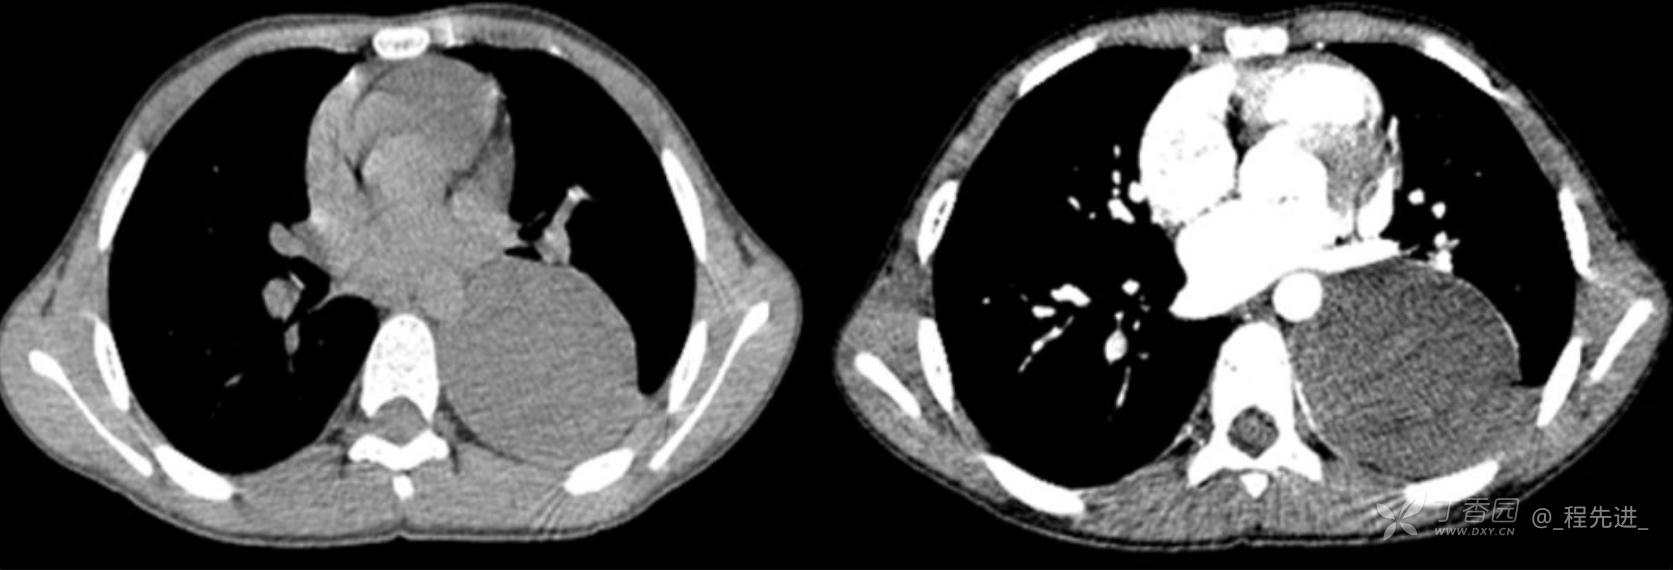

11月特别精彩病例|胸片示“左侧胸腔包裹性积液”,CT增强你诊断啥?【病理已公布】

呱呱叫了 等 3 位达人已点赞男,11岁,患儿因其爷爷近期在我院诊断“肺结核”,于外院行结核筛查,胸片示“左侧胸腔包裹性积液”,近期无咳嗽、发热、纳差、盗汗、乏力、胸痛、胸闷、气促不适,精神反应可,为求明确“左侧胸腔包裹性积液”病因,遂来我院门诊就诊,门诊以“胸腔积液查因”收住入院。发病以来,精神尚可食欲如常,大便如常,小便量如常,体重无明显变化